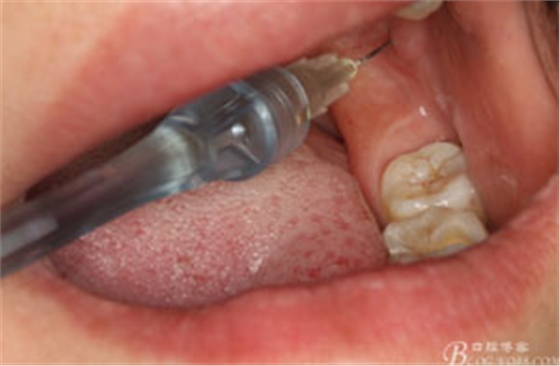

圖4.行下頜無(wú)痛阻滯麻醉

圖5.加局部浸潤(rùn)麻醉